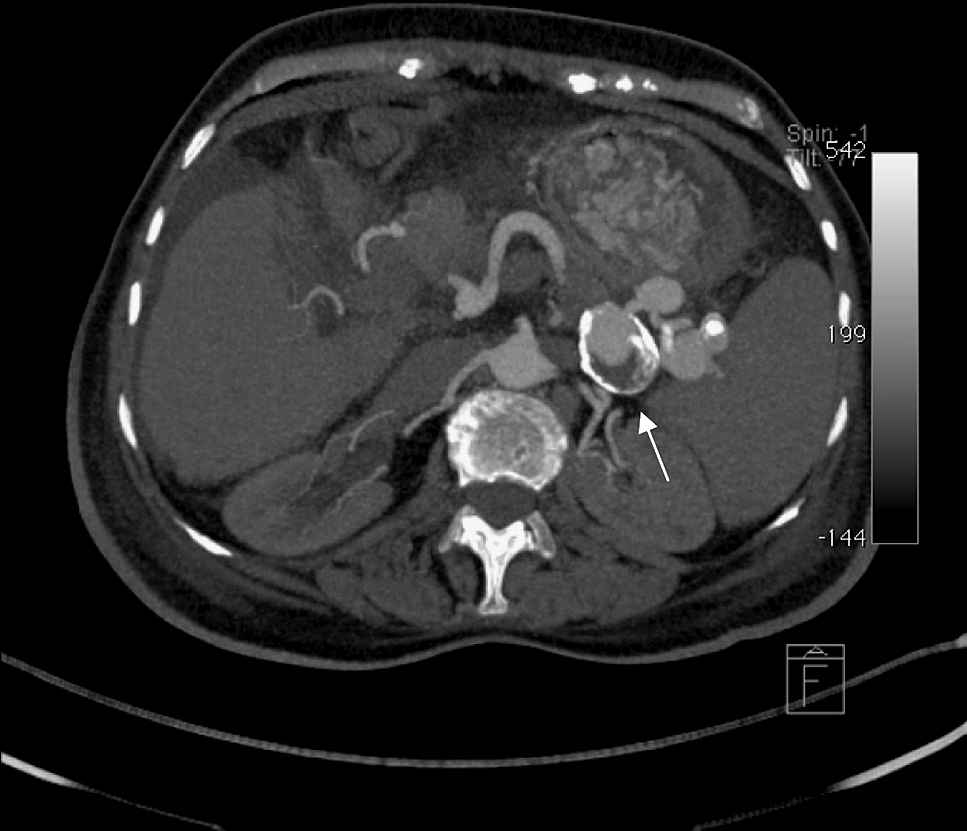

A 69 year old female with a 10 year history of Idiopathic Thrombocytopenic Purpura (ITP) being treated with 60 mg of prednisone per day was admitted for worsening of her clinical condition and abdominal left upper quadrant pain. Contrast-enhanced computed axial tomography exam of her abdomen and pelvis revealed six calcified distal splenic aneurysms with partial luminal thrombosis (Fig. 1–4).

Contrast enhanced axial MIP image, in arterial phase, demonstrates several hilar splenic aneurysms. The largest and pointed one in this figure has an egg-shaped mural calcification and a partial luminal thrombosis.

This contrast enhanced axial MIP image, in portal phase, also shows the hilar splenic aneurysms, still well opacified. This may mean a slow arterial flow.